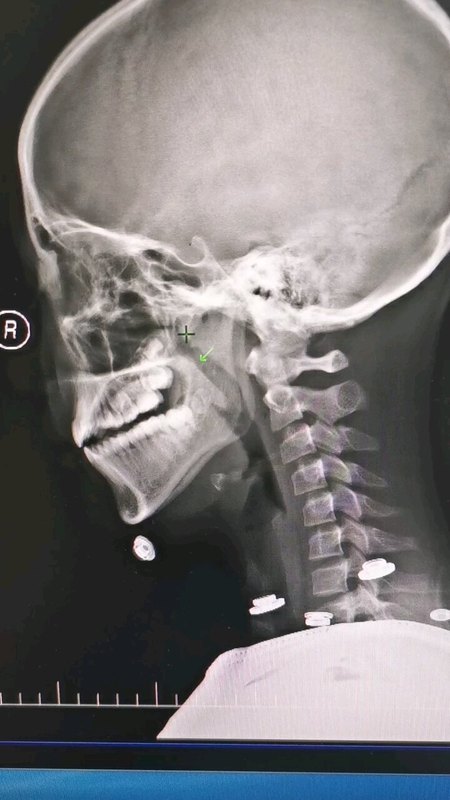

腺样体肥大、扁桃体肥大及鼻甲肥大手术策略

儿童腺样体肥大到底要不要切除?

腺样体肥大,切还是不切?

腺样体面容的六大特征

谈谈腺样体肥大手术的必要性

扁桃体腺样体肥大需要手术切除吗